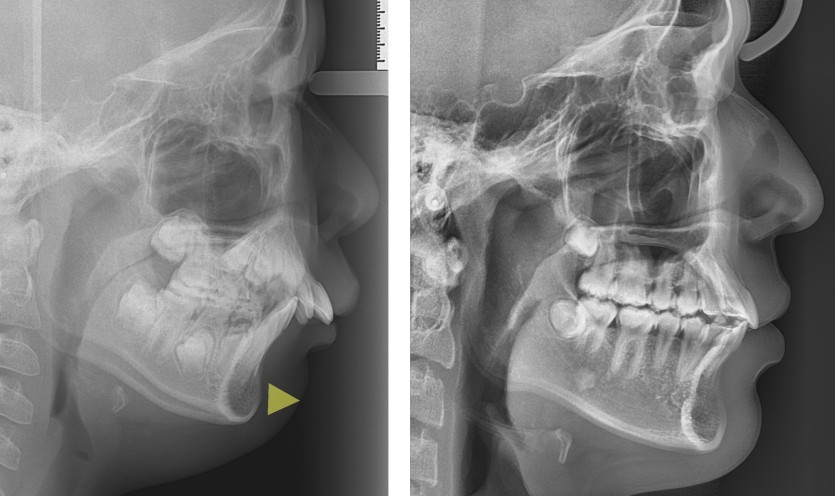

무턱의 성장조절 치료 130회

무턱을 지닌 청소년 환자들의 경우에는 안면 골격의 성장조절 치료를 진행할 수 있습니다.

사춘기는 성장이 급속하게 일어나는 시기이므로 상악의 성장을 헤드기어라는 장치를 통해 제한하고

바이오네이터라는 장치로 하악의 성장을 유도합니다.

헤드기어의 치료는 예측 가능하며 협조가 충분할 경우 상악의 성장 제한을 기대할 수 있으나

바이오네이터는 치료 반응이 좋을 수 있는 안모인지를 분류해야하며

하악의 성장이 적극적으로 일어난다기보다는 치조골의 변화를 통해 안면 골격의 편차를 극복하는 방법입니다.